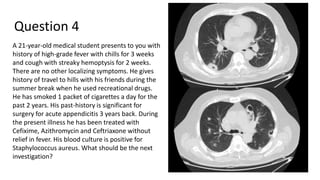

Question 4

A 21-year-old medical student presents to you with

history of high-grade fever with chills for 3 weeks

and cough with streaky hemoptysis for 2 weeks.

There are no other localizing symptoms. He gives

history of travel to hills with his friends during the

summer break when he used recreational drugs.

He has smoked 1 packet of cigarettes a day for the

past 2 years. His past-history is significant for

surgery for acute appendicitis 3 years back. During

the present illness he has been treated with

Cefixime, Azithromycin and Ceftriaxone without

relief in fever. His blood culture is positive for

Staphylococcus aureus. What should be the next

investigation?

Answer 4

A 2D Echocardiography

He seems to have developed an unfortunate complication from his vices!